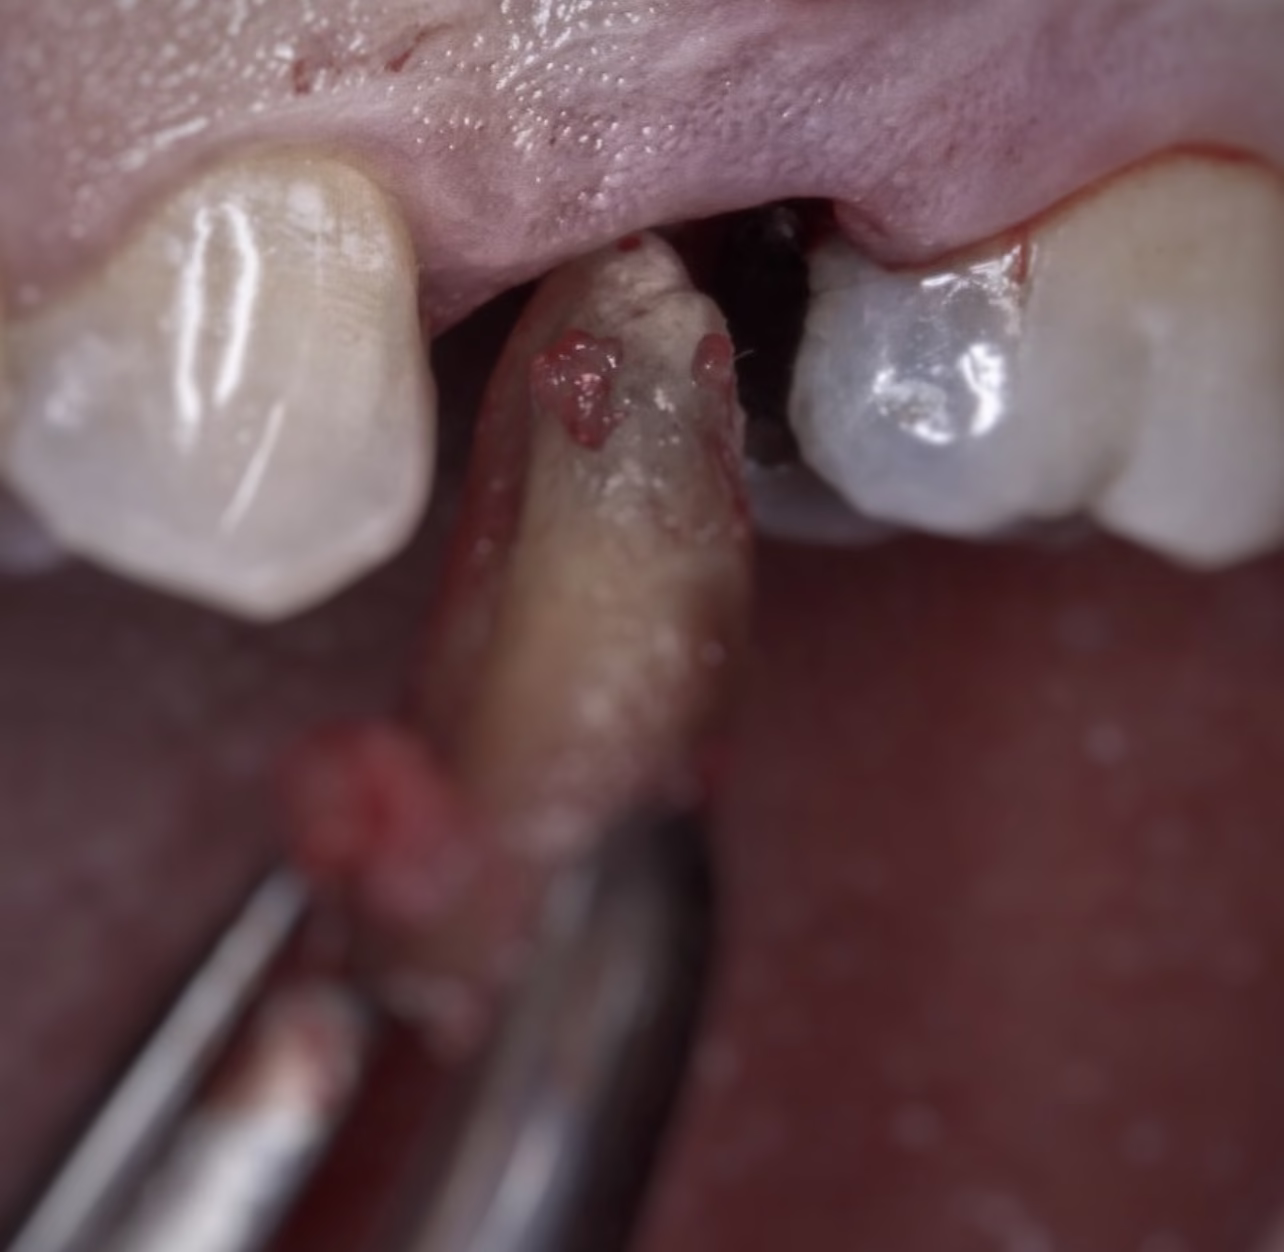

Extracción quirúrgica:

- Se aplica en casos complejos: muelas del juicio incluidas, raíces fracturadas o dientes retenidos.

- Requiere levantar encía, en ocasiones desgastar hueso y puntos de sutura.